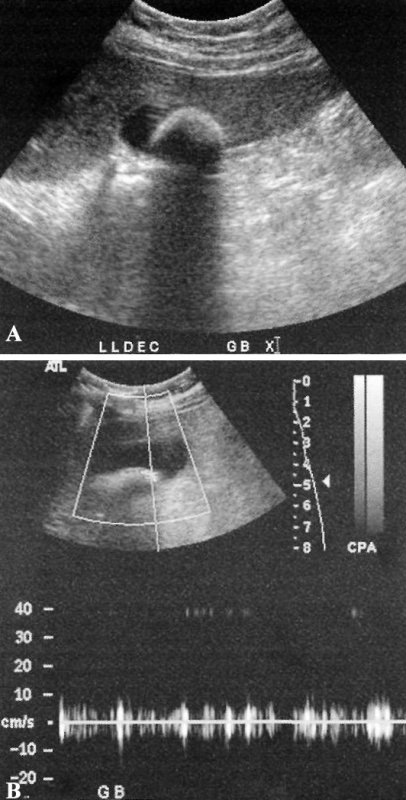

Краевой артефакт образуется на поверхности сильного отражателя, на изображении похож на кальцифицированную структуру (например, кортикальный слой костной ткани, камни в желчном пузыре и др) (фото 7).

УЗИ: Камень в желчном пузыре с краевым артефактом

Фото 7. Камень в желчном пузыре с краевым артефактом. А – черно-белое изображение крупного камня в желчном пузыре. В – усиленное допплерографическое изображение, на котором наблюдается имитация потока на поверхности камня. Спектральная запись на фото В демонстрирует только шум и отсутствие потока. Это характерно для цветной допплерографии и для усиленного допплеровского исследования.